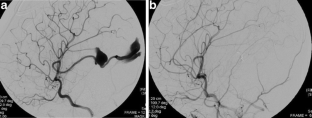

Intracranial pial arteriovenous fistulas (AVF) are rare vascular malformation especially in the first 2 years of life. The pathology in this age group is associated with greater morbidity and mortality. We report a rare case of 36-day-old male infant with a pial AVF associated with an arterial aneurysm, who presented with intraventricular hemorrhage and hydrocephalus. In addition, an online review of the literatures on pediatric pial AVF was performed using PubMed on published case reports and articles from 1980 to April 2013.

Fig. 2